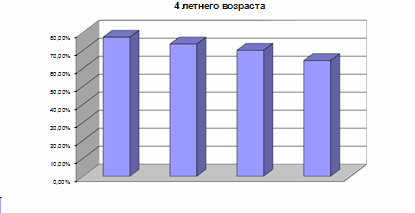

Чтобы профилактика давала наибольший эффект, необходимо одновременно воздействовать на все основные факторы риска в развитии зубов. Профилактика кариеса зубов препаратами фтора получила наибольшее распространение в мире, это - единственный метод, позволивший достичь реального снижения заболеваемости.

Но на территории Р.Ф. существуют и другие проекты, которые могут решить эту проблему. Например, в Воронежской началась программа создания фторосодерщащего молока. В результате которой стоматологические заболевания сократились